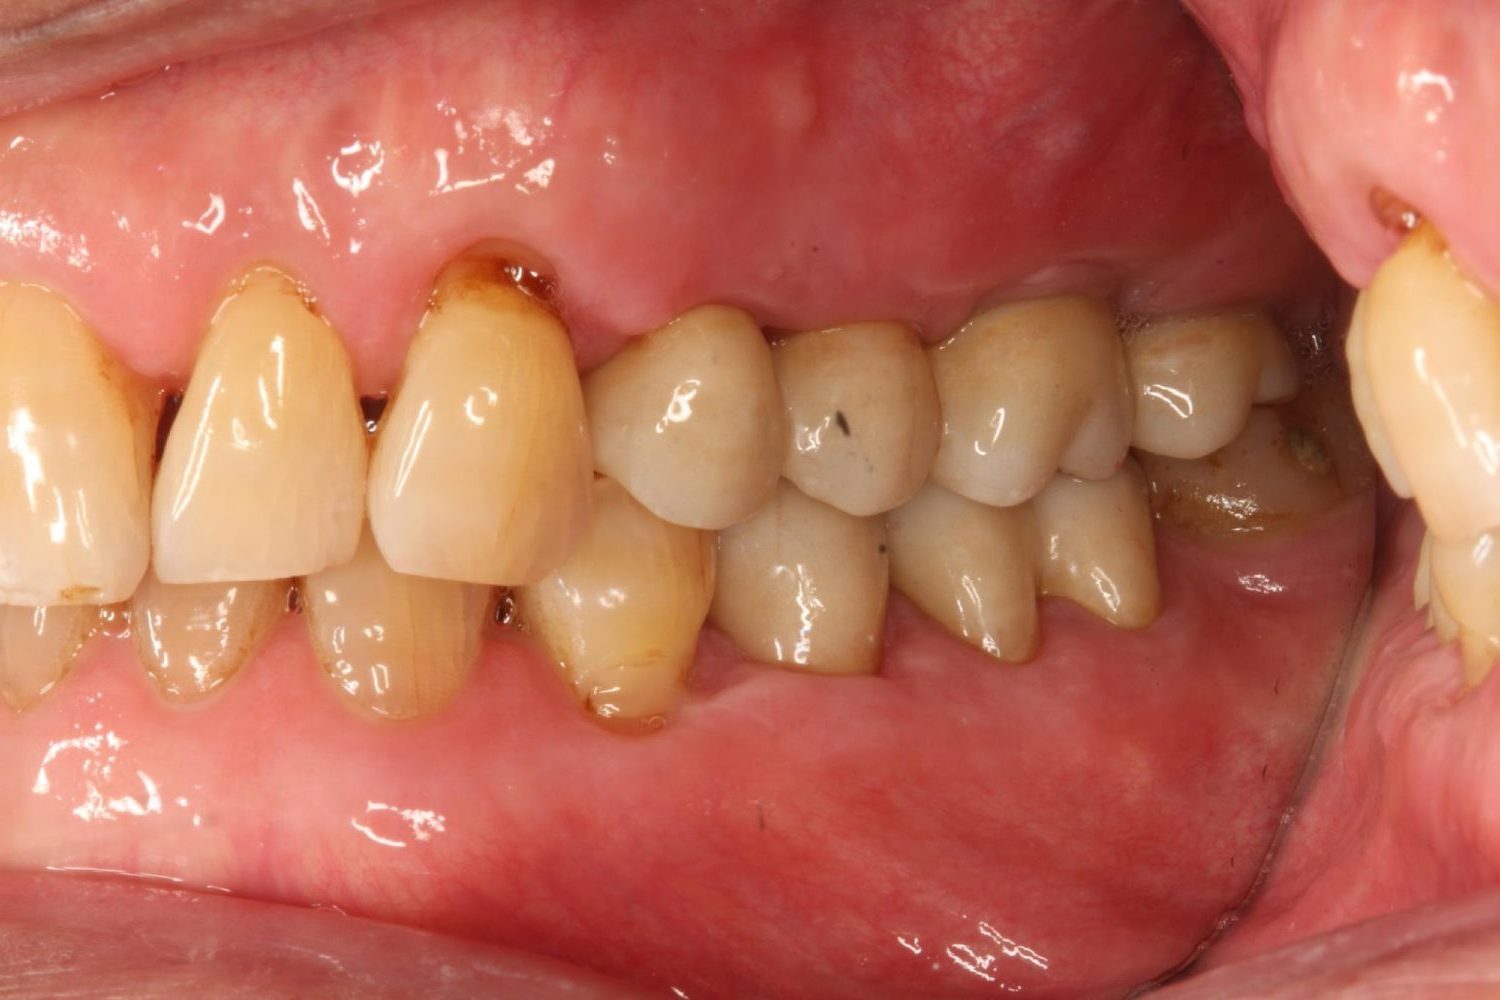

インプラント治療の症例紹介⑤

Before

After

主訴

歯肉腫脹、咬めるようにしたい

治療内容

重度歯周病により全ての残存歯保存不可能な状態。上下顎ボーンアンカードブリッジによる咬合再構成。

治療費

12,621,400円(税込)

治療期間

22ヶ月

通院回数

28回

想定されたリスク

※上部構造の形態が複雑になるため清掃が難しくなる、インプラント周囲炎の恐れがありました。

濱 仁隆先生

浜歯科

上顎8本下顎7本のインプラント体埋入によるボーンアンカードブリッジ。